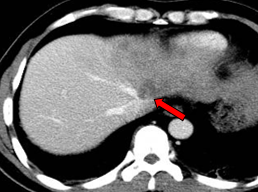

2011-02-12复查CT示:肝左叶碘油散在沉积,病灶大部分仍有活性,肝右后叶病灶未见碘油沉积;门静脉癌栓较前进展,累及主干及右支;肝左静脉及下腔静脉内癌栓无明显变化。AFP:26802 ng/ml。

2011-04-20复查CT示:肝左叶病灶较前缩小,肝右叶病灶见碘油致密沉积;门脉癌栓左支较前缩小,右支癌栓消失;下腔静脉、肝左静脉癌栓消失。AFP:4983 ng/ml。

2011-06-09(第二次TACE后4个月)复查肝脏CT示:肝左叶病灶继续缩小,但仍有肿瘤残留。AFP:8137 ng/ml(较上次复查明显升高)。

2011-08-15复查CT示:肝左叶病灶大小较前相仿,仍有肿瘤残留。